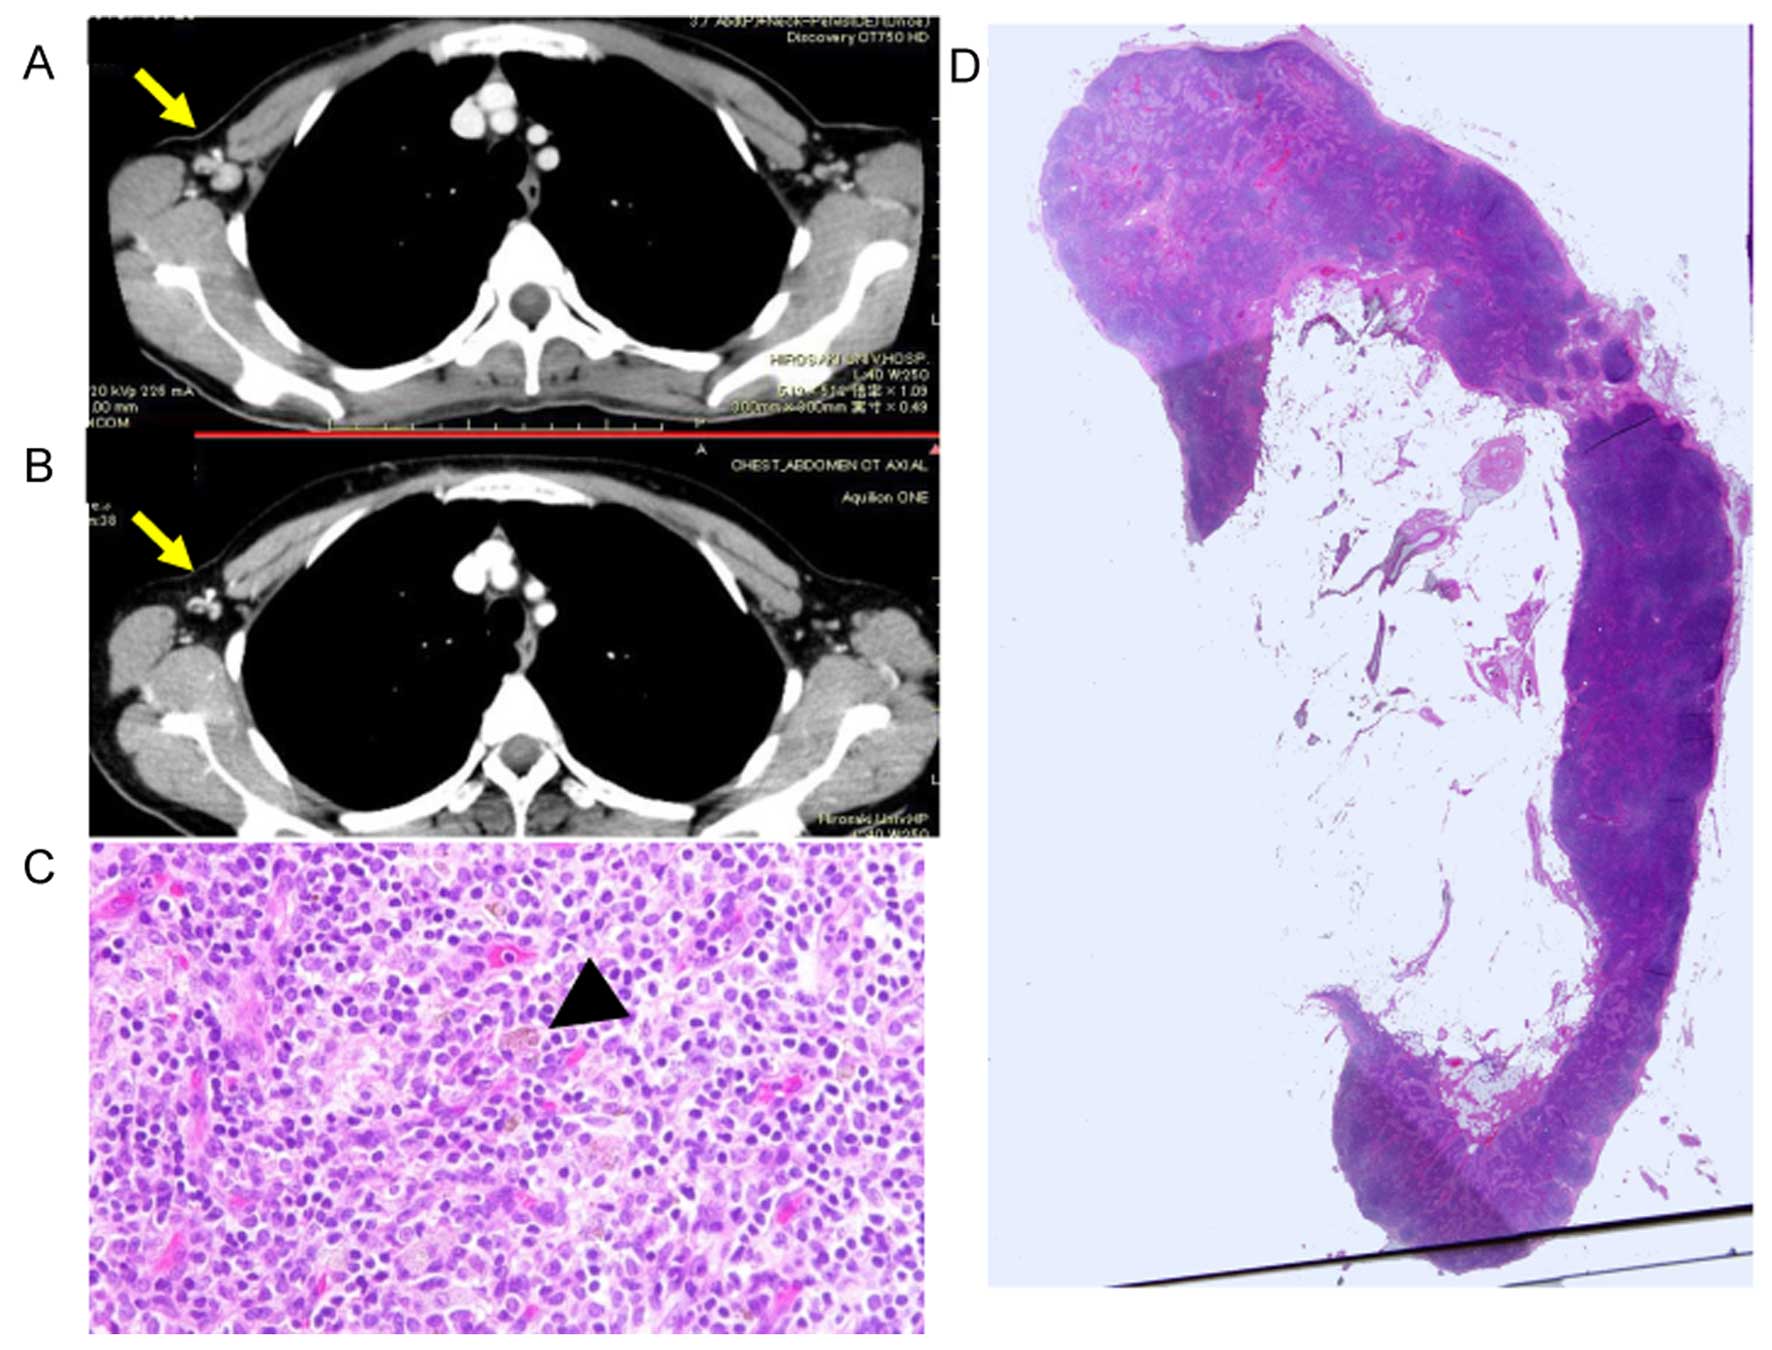

A 62 Year Old Male Patient With Histologically Verified Malt